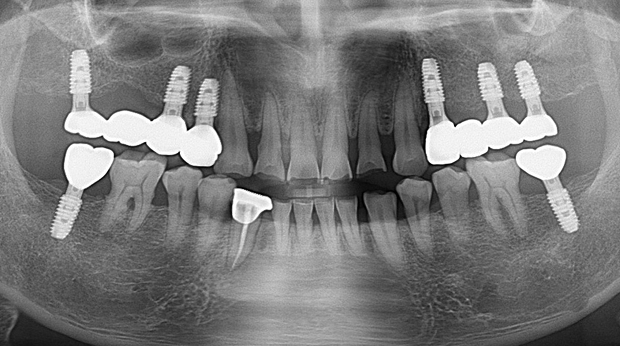

임플란트와 사랑니 발치는 외과적 시술로 잇몸을 절개하는 외과적 시술은

짧으면 짧을 수록 시술 후 붓기와 통증이 최소화됩니다.

치과의사 경력 14년차 구강외과 전문의가 빠르고 안전하게, 아프지 않게 수술해 드립니다.

치과경력 14년차 구강외과 전문의